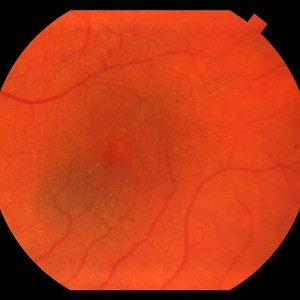

Choroidal Nevus

Color fundus image of a small choroidal nevus near the macula.

Photographer: Olivia Rainey

Imaging device: Topcon50dx

Condition/keywords: 20 degrees, choroidal nevus, color fundus photograph, color photo, macula